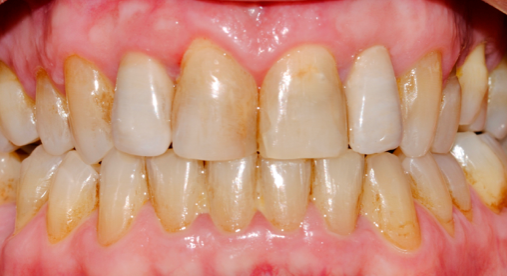

Os enseñamos este nuevo caso el Dr. Arturo Sánchez Colodro en nuestra clínica dental de Jaén, nos muestra un caso de cirugia plástica periodontal con injerto de tejido conectivo subepitelial en recesiones inferiores en paciente con sensibilidad y recesión de las encías de los dientes inferiores por trauma oclusal y cepillado inadecuado. Este caso ha sido tratado con la última y más avanzada tecnología en digitalización dental. Mostramos el resultado después de la operación realizada, el resultado en la revisión un año después y la comparativa del antes y después.

Revisión al año: